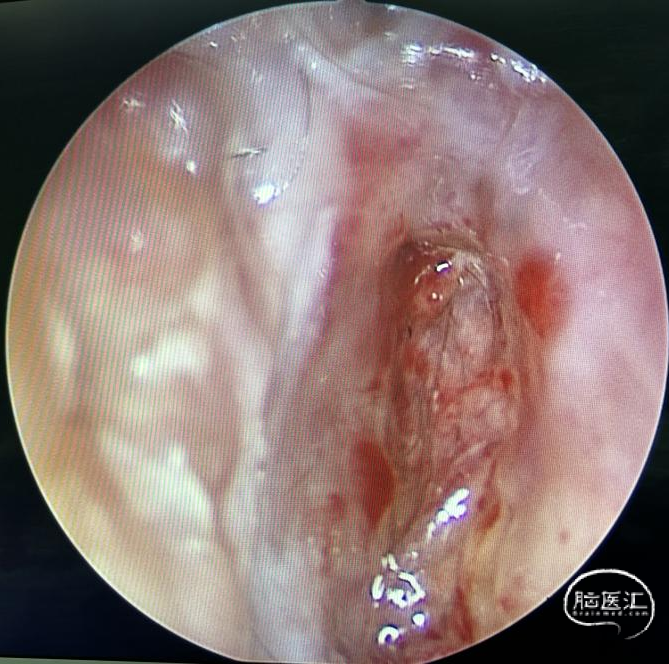

陈卓鹏医师在内镜和显微镜中的协助为手术的顺利完成提供了帮助。肿瘤挤压脊髓圆锥,与其及马尾神经根粘连紧密,显微下切除视野直视下肿瘤,内镜辅助下予以切除肿瘤两端,马尾神经根完好保留,内镜下操作直视外部分肿瘤,减少对神经根的牵拉,降低了术后患者不适发生的机率。术后患者腰部下疼痛及肢体活动障碍症状明显改善。